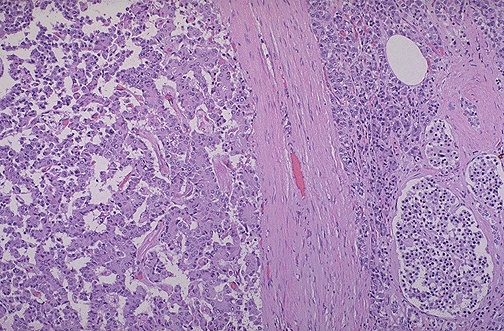

| The islet cell adenoma at the left contrasts with the normal pancreas with islets at the right. Some of these adenomas function. Those that produce insulin may lead to hypoglycemia. Those that produce gastrin may lead to multiple gastric and duodenal ulcerations (Zollinger-Ellison syndrome). |